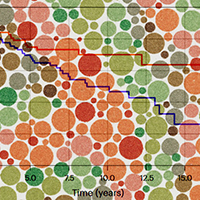

Американские исследователи провели лонгитюдное когортное исследование и выяснили, что расстройство цветового зрения связано с худшей выживаемостью при раке мочевого пузыря, но не толстой и прямой кишки. Статья опубликована в журнале Nature Health с комментарием приглашенного специалиста.